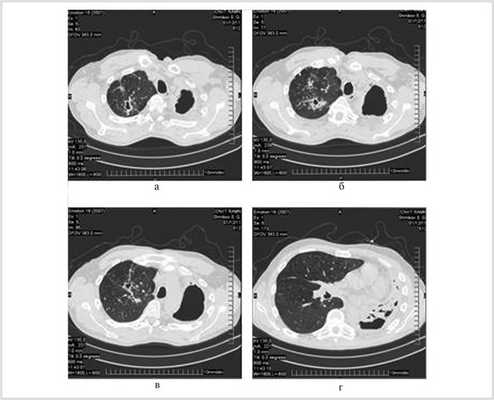

Из 85 операций, выполненных 50 нашим пациентам, 61 произведена из минидоступа с применением видеоторакоскопии. При этом для прошивания легочной ткани использовался сшиватель органов для малоинвазивной хирургии, разработанный проф. Д.Б. Гиллером совместно с фирмой "Уникон" (Россия). Примером подобной операции может служить наблюдение повторной резекции после ранее произведенной нижней лобэктомии слева (рис. 1-4 ).

Результаты и обсуждение

При выполнении 50 повторных резекций легкого у 50 пациентов мы обнаружили плевральные сращения во всех случаях, при этом в 2 (4%) они были ограниченными, в 13 (26%) субтотальными (более 1 / 2 поверхности плевральной полости) и в 35 (70%) тотальными. Длительность операции составила в среднем 220,7 мин, средняя интраоперационная кровопотеря - 346,6 мл. Гемотрансфузий удалось избежать у всех больных.

При компьютерной томограмме выявлены цирротические изменения левого легкого с обширной полостью эмпиемы и множественными мелкими полостями в коллабированном легком. Правое легкое уменьшено в объеме за счет фиброзных изменений верхней доли, в которой определялись три каверны диаметром до 2 см, имелось очаговое обсеменение нижних долей (рис. 1).

Рис. 1. Компьютерные томограммы больного Ш. до операции.